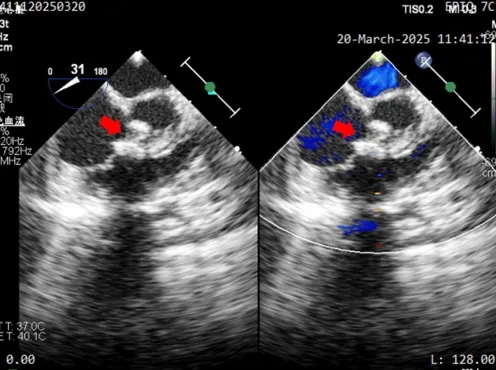

术后1个月随访,二维超声心动图及心脏彩色多普勒所见:

1、心房正位,心室右袢,房室连接正常,心室及大动脉连接正常。

2、各房室大小尚可。

3、室间隔、左室后壁、右室前壁心肌厚度正常。

4、房间隔完整,心房水平未见分流。

5、室间隔见封堵器回声,位置固定,伞面光滑,塑性良好,室水平未见分流。

6、左室流出道未见异常,主动脉瓣回声正常,启闭活动良好。

7、右室流出道心肌未见肥厚,肺动脉瓣回声正常,启闭活动良好,主肺动脉未见异常。

8、余瓣膜形态、结构及活动未见异常。

9、升主动脉、主动脉弓横部、主动脉弓降部未见狭窄,降主动脉血流正常。